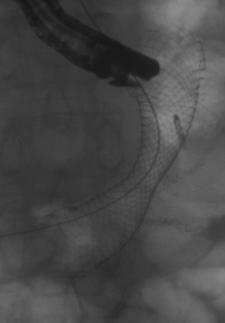

Insertion of a stent into the esophagus

Esophageal Stenting

A stent may be inserted in the esophagus to enhance swallowing

In some patients, an esophageal tumor can prevent the swallowing of solid and/or liquid foods. In these cases, esophageal stenting can be performed. It involves the use of an endoscope and x-rays to help place a metal stent across the esophageal tumor and helps to force the tumor up against the wall of the esophagus.

The stent has a hollow center that permits the passage of pureed foods and liquids into the stomach so the patient can still eat and get nutrition. The placement of a stent does not interfere with the patient's ability to have chemotherapy or radiation treatment. In some cases, the stent can later be removed if the disease responds to treatment. For more about esophageal stenting, visit Advanced Interventional Endoscopy.